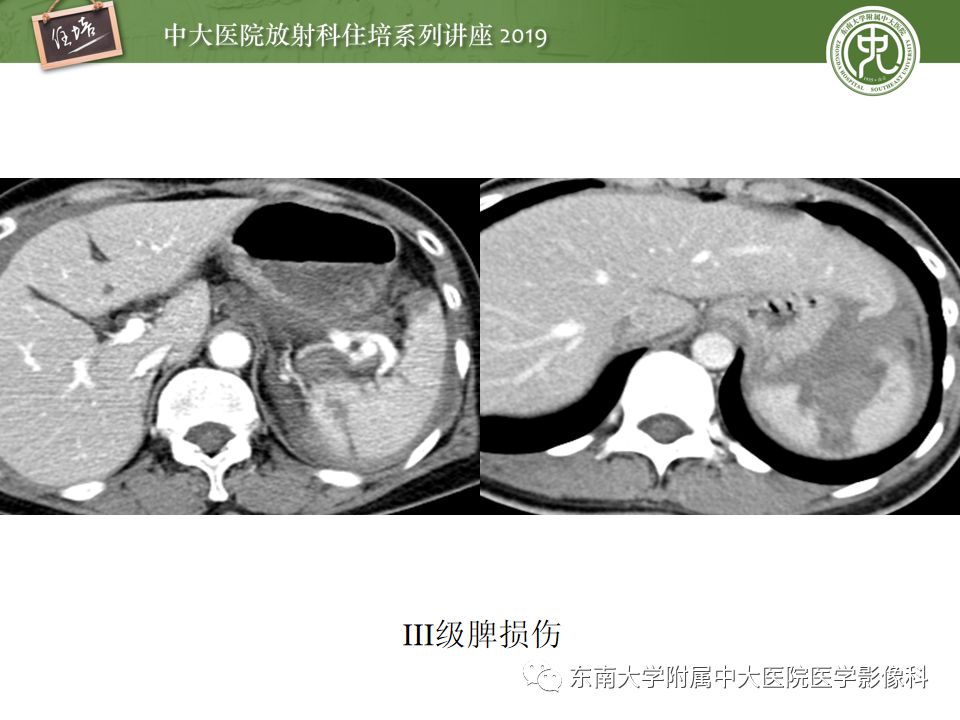

腹腔实性脏器钝性外伤影像诊断